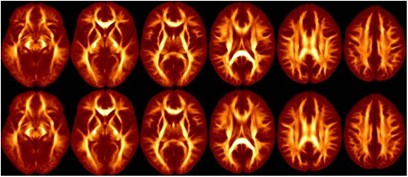

Patients did not differ significantly from healthy volunteers in distributions of age, sex, parental social class, handedness, race, or years of education (Table 1). An illustration of the intersubject registration of the FA maps for patients and healthy volunteers is provided in Figure 1 and the average SPGR images are provided in Figure 2. Voxelwise analysis of the white matter revealed three regions of higher FA in the right and left frontal white matter and one region of lower FA in the left cerebellum in bipolar patients compared to healthy volunteers (Table 2; Figure 3). Circular regions of interest placed on the raw FA maps in the left (t=2.43, d.f.=66, p=0.02) and right (t=1.94, d.f.=66, p=0.06) frontal white matter (corresponding approximately to clusters 2 and 3, respectively) supported the voxelwise results. Independent group t-tests revealed significant group differences in radial diffusivity in clusters 1–3 and axial diffusivity in clusters 1 and 4 (Tables 3 and 4). Effect sizes for group differences in axial and radial diffusivity ranged from 3 to 18%. Repeated-measures analysis of variance for axial and radial diffusivity measures revealed no significant group-by-region interaction for any of the four FA clusters that differed significantly between groups.